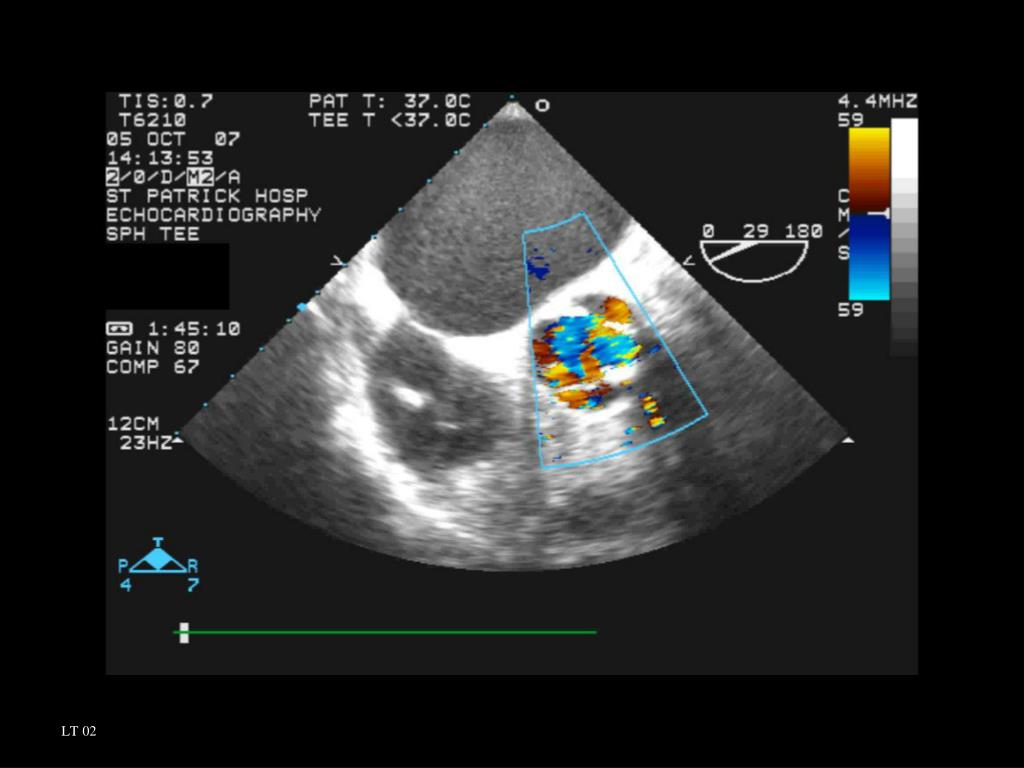

Aortic valve sclerosis with mild aortic regurgitation doctorvisit Is A Trileaflet Aortic Valve Bad The idea is based on mimicking the native trileaflet aortic valve, while maintaining the durability of a mechanical valve. “these findings show that an aortic root area/height ratio > 10 cm2/m has significant and independent prognostic value in stratifying risk among patients with trileaflet aortic valve and dilated. This causes blood to flow backward from the body's main artery, called. Is A Trileaflet Aortic Valve Bad.